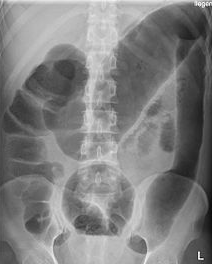

What is the abnormality on this x-ray?

Foreign body (cholecystectomy clip)